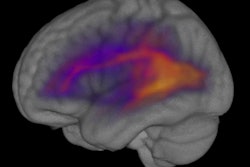

The findings are relevant for "visual neglect," which can occur after a stroke or other brain injury. People with visual neglect can see all the objects and events in their visual field, but they often aren't aware of the events on the affected side.

"Visual attention has to do with the internal management of information," Krauzlis said. "The connection with the superior colliculus is important because we think it could be acting like a spatial index that helps you keep track of the information that you're trying to process."